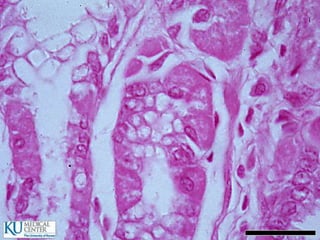

ID: Células cilíndricas

 Cada célula tiene un borde en cepillo

 Borde PAS positivo en relación con el Glucocáliz

 El glucocáliz es resistente a los proteolíticos y

mucolíticos

 Las microvellosidades tienen un centro con filamentos

finos de actina que se mezclan con el velo terminal que

tiene miosina

 Absorben azúcares y aminoácidos por un proceso

activo y pasan al espacio extracelular por difusión

pasiva

 Absorven lípidos: Los lípidos primero son captados por las

miscelas intraluminales de sales biliares, que los estabilizan

en una emulsión y los transportan al borde estriado donde

difunden al interior de la célula como ácidos grasos

 Estos ácidos se unen a un componente glucoproteínico

(apoproteína) en el retículo de golgi

 Las gotitas de quilomicrones de lipoproteína así formados

pasan hacia los espacios intercelulares y se dirigen hacia

abajo para atravezar la lámina basal y entrar a los vasos

linfáticos (quilíferos), de la lámina propia